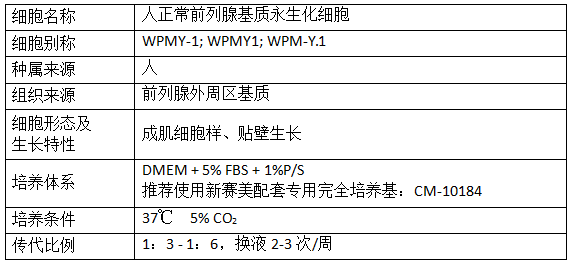

产品信息: